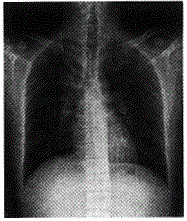

患者男,20岁。因“发热、咳嗽21天”入院。查WBC 4.47×10

/L,中性粒细胞45%。体查:体温37.6℃,双肺呼吸音粗,未闻及干湿啰音。

患者男,20岁。因“发热、咳嗽21天”入院。查WBC 4.47×10/L,中性粒细胞45%。体查:体温37.6℃,双肺呼吸音粗,未闻及干湿啰音。

该例的特点是

A渗出病变为主

B纤维性病灶为主

C增殖性病灶为主

D钙化型病灶为主

E混合性病灶为主